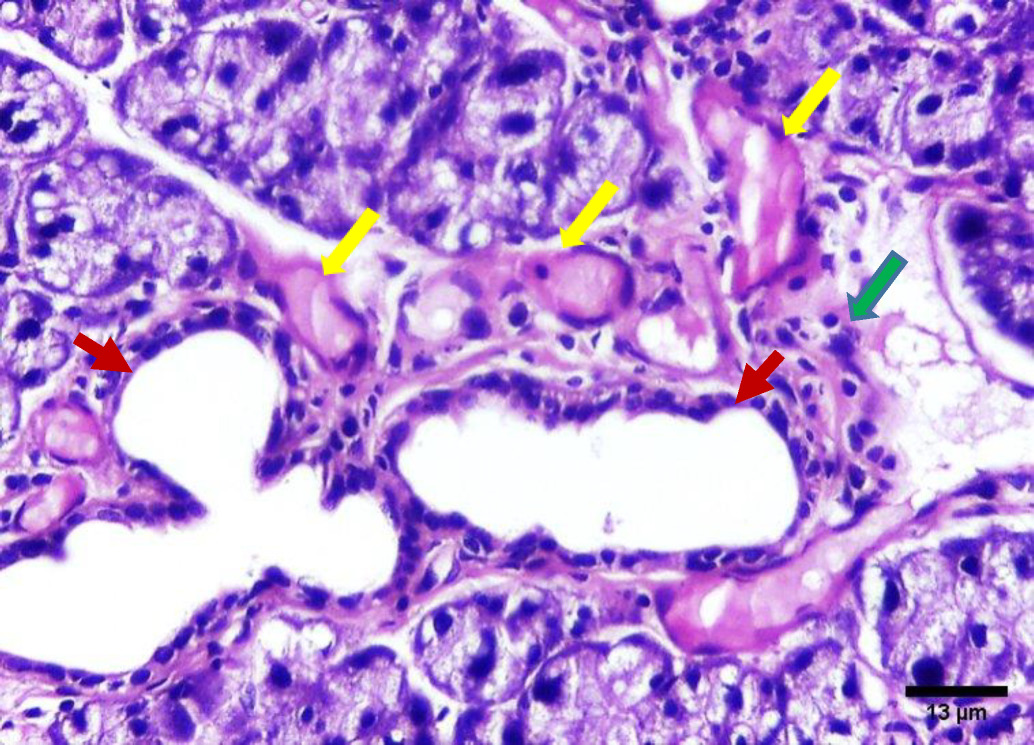

On the contrary, the H&E stained sections of group B (irradiated group receiving treatment) on day 14 showed improved degenerative changes that further improved at day 30. The positive outcome is demonstrated by decreased acinar shrinkage and cytoplasmic vacuolization in some acini, others suffered from degeneration in a few areas, also nuclear anisonucleosis and poikilonucleosis were less pronounced in this group. Mitotic figures were observed within some acinar cells. The striated and intercalated ducts maintained their form and remained intact. Few excretory ducts showed areas of thinning in their epithelial lining. The connective tissue appeared with fewer areas of fibrosis and few chronic inflammatory cells infiltrated. Few blood vessels were dilated and engorged with RBCs (Figure 4, Figure 5).

In the current investigation, shrinkage of some serous acini, fewer areas of acinar degeneration and fewer cytoplasmic vacuoles were observed within some serous acini in group B which received vitamin B17 (day 14 and day 30). The changes on day 30 were less than that on day 14. These changes were similar to findings reported by Qadir and Fatima where amygdalin acts as an antioxidant and a scavenger of the harmful and highly hydroxyl radicals by maintaining a healthy body pH.20

Intercalated and striated ducts showed no detectable changes in our study in group A (day 14 and day 30) and group B (day 14 and day 30). This could be attributed to the powerful regenerative properties of the ductal structure of the salivary gland.22

Milazzo et al. reported that vitamin B17 which is a main component of GAK has many potentialities in addition to its protective effect against cancer. It boosts immunity and eliminates harmful cells as it acts as an antioxidant. The protective properties could account for the decreased fibrosis in group B (day 14 & day 30) in this study.6 This interpretation is supported by Abdel-Rahman who carried out a study on rats suffering from induced hepatic fibrosis and reported that the addition of GAK to rats’ diet inhibited acute hepatocellular injury and fibrosis.12

The presence of blood vessels engorged with red blood cells was observed in this investigation in group A (14 and 30 days) which decreased in group B (14 & 30 days). These findings were in agreement with the results of Redman who found thinning and discontinuity in the endothelium lining of blood vessels of the parotid salivary gland of rats that was subjected to irradiation, leading to a compromised blood supply.26

Chronic inflammatory cells and dilated blood vessels decreased in the treatment group at 14 days with continued improvements at day 30 compared to controls., These observations may be mediated by the anti-inflammatory properties of GAK, where Minaiyan, Ghannadi, Asadi, Etemad, and Mahzouni found GAK treatment in treating colon inflammation in rats also resulted in a decrease in inflammatory cells.28

Mitotic figures were observed in group B specifically on day 30. This finding was explained by Mohamed, El-Sakhawy, Sheriff, and Shredah, who assumed that mononuclear cells duplicate DNA while undergoing endomitosis. Therepeated prevalence of mitotic figures can be explained by being an adaptive trial of the acinar cells to heal after injury.29